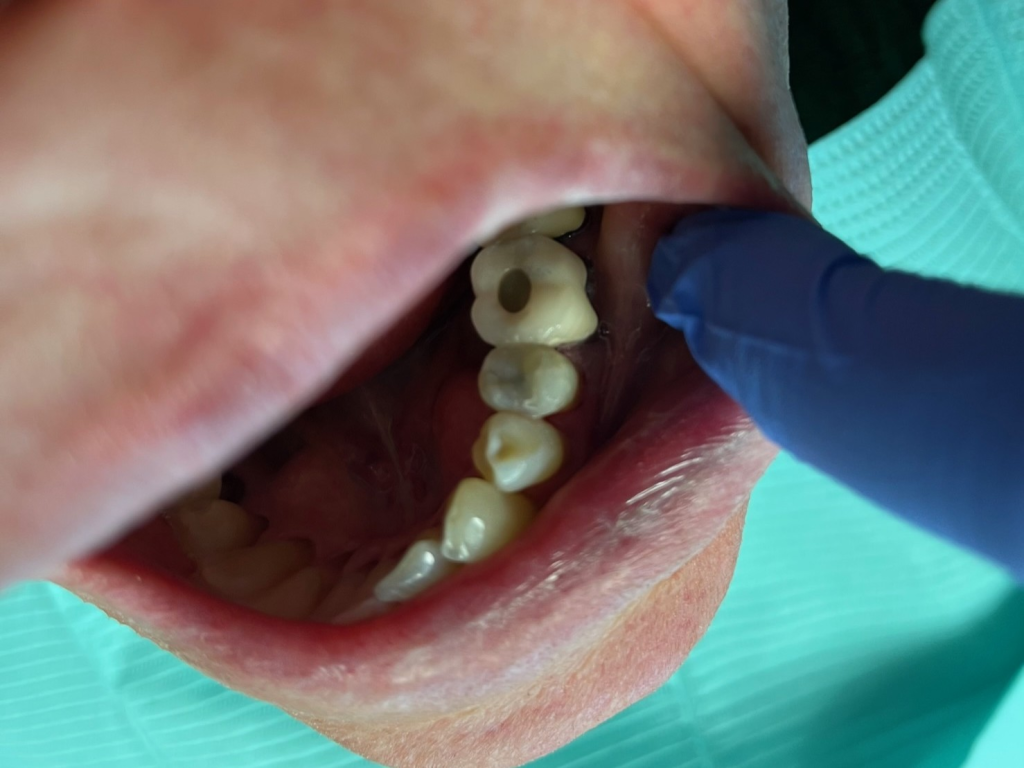

5

DentXpinTM repair.